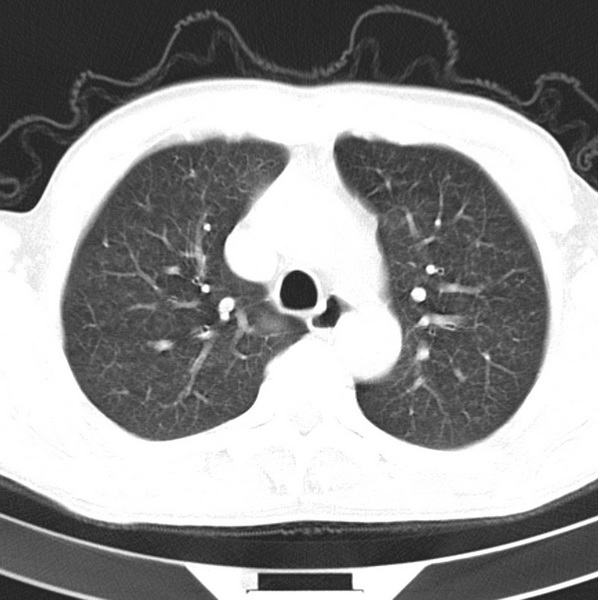

男、48、咳嗽。

胸片示双肺纹理紊乱,行胸部ct检查。

右肺下叶基底段结节影,双肺粟粒样阴影,ct值测量约-20hu左右,可能不准。

层厚层距为4mm左右,病灶轴面最大径约1cm左右。